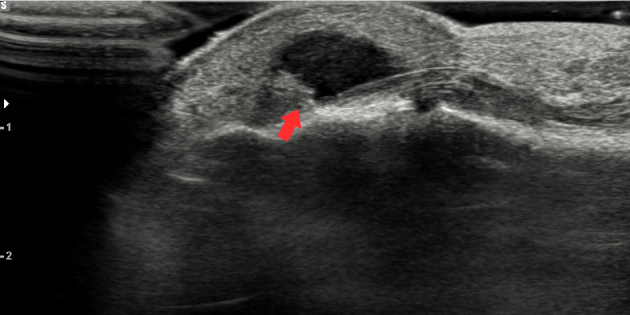

거대 세포종

힘줄 막에 생기는 종양으로 손가락에는 악성종양이 생기는 경우가 매우 드물기 때문에 보통은 양성의 종양을 말합니다. 양성의 성격을 보이지만 주변 조직을 파괴하고 높은 재발률을 나타내며 악성의 성격을 일부 보여서 반드시 치료를 해야 하는 종양입니다.

결절종 다음으로 많이 발병되는 종양으로 주로 손가락에 나타나지만 무릎이나 엉덩이(고관절)에 발병하는 경우도 있습니다.

거대세포종 초음파 영상 사진